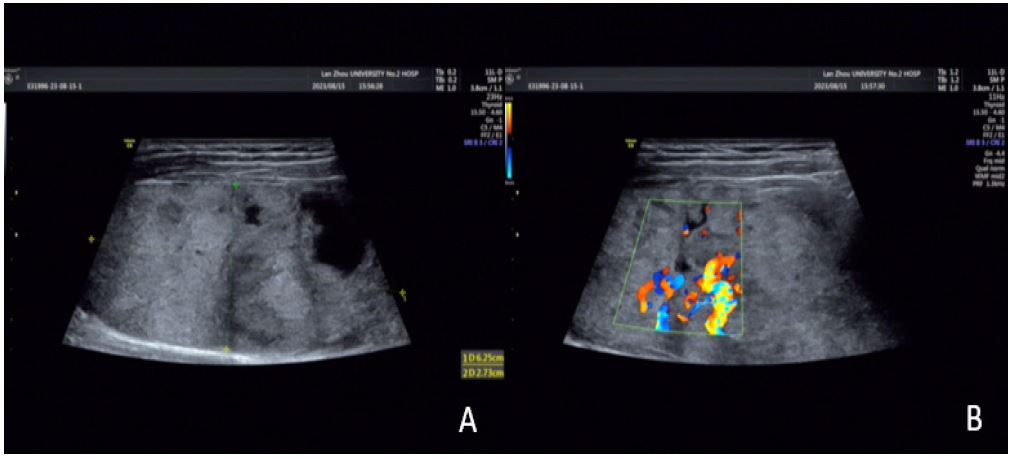

Imaging findings: Ultrasound revealed multiple mixed-echo nodules in both thyroid lobes: Left lobe: 2.2×1.7 cm (predominantly solid); Right lobe: 2.7×1.9 cm (predominantly solid).

Features: aspect ratio <1, regular shape, well-defined margins, peripheral and intranodular vascularity (C-TIRADS 3). Contrast-enhanced neck CT suggested nodular goiter with multiple adenomas.

Figure 2: (A) a cystic solid mass of about 2.2 x 1.7 cm in size is seen in the left lobe of the thyroid gland (shown by arrows), with a regular morphology, clear borders, uneven internal echogenicity, and a hypoechoic halo is seen around it; (B) a small amount of short rod-shaped blood flow signals can be seen inside and around the mass (shown by arrows).